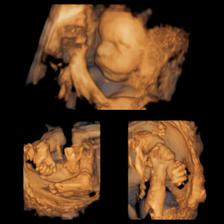

10.05.2016 : morfologický ultrazvuk Martin, MUDr. Grochal (19tt+1)